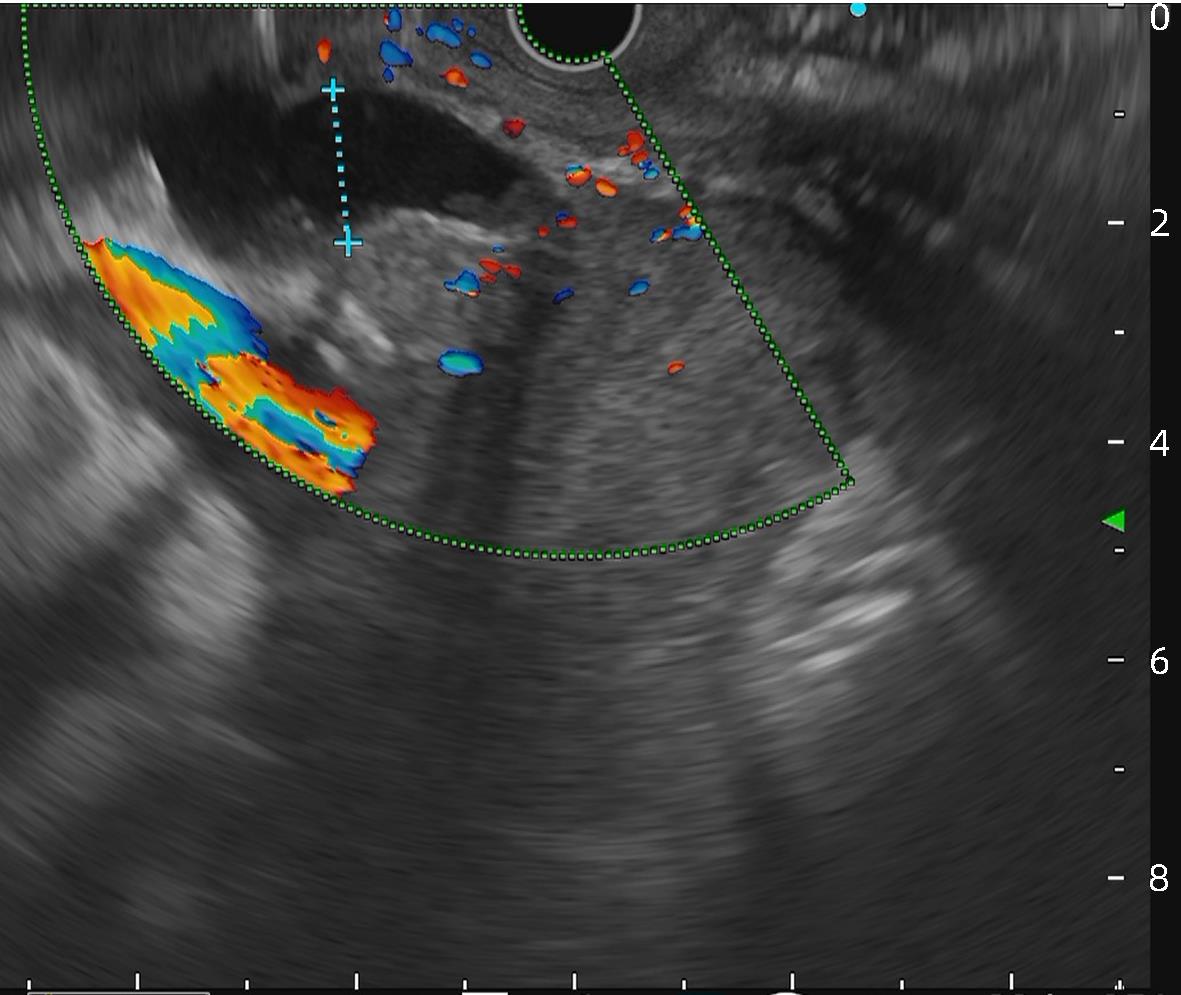

The preliminary therapeutic effect of endoscopic ultrasound-guided tissue adhesive injection with the assistance of metal clips in treatment of cirrhotic patients with gastric varices and gastric-renal shunt

Jiali MA, Zhenglin AI, Julong HU, Yu JIANG, Yuling ZHOU, Xiuxia LIANG, Hongshan WEI, Ping LI

2024, 40(4): 734-738. DOI: 10.12449/JCH240415

Abstract(1116) HTML (309) PDF (1036KB)(61)

Abstract:

Objective  To investigate the safety and efficacy of endoscopic ultrasound-guided tissue adhesive injection with the assistance of metal clips in the treatment of cirrhotic patients with gastric varices and gastric-renal shunt (GRS).  Methods  The patients who attended Beijing Ditan Hospital, Capital Medical University, due to liver cirrhosis and gastric varices from February to June 2023 were enrolled, and all patients were confirmed to have GRS and received endoscopic ultrasound-guided tissue adhesive injection with the assistance of metal clips. The primary evaluation index was alleviation or disappearance of varicose veins after surgery, and the secondary evaluation indices were surgical completion and complications.  Results  A total of 11 patients were enrolled in this study, among whom there were 7 male patients and 4 female patients, with a median age of 55 years. Of all patients, 1 had Child class A liver function, 7 had Child class B liver function, and 3 had Child class C liver function. The maximum (median) diameter of the shunt was 8 mm, and the minimum (median) diameter of the shunt was 4 mm. The median blood flow velocity of the target vessel was 11 cm/s before treatment and 5 cm/s after occlusion with metal clips. The median amount of tissue adhesive injected was 2 mL, and the amount of lauromacrogol used was 1 mL. Disappearance of blood flow signals was observed in all patients after surgery (100%), and the success rate of surgery was 100%. No patient experienced rebleeding after follow-up for 6 weeks. Gastroscopy at 1 month after surgery showed that gastric varices were eradicated or almost disappeared in 9 patients and were alleviated in 2 patients.  Conclusion  Endoscopic ultrasound-guided tissue adhesive injection with the assistance of metal clips is a feasible, safe, and effective treatment method for cirrhotic patients with gastric varices and GRS.